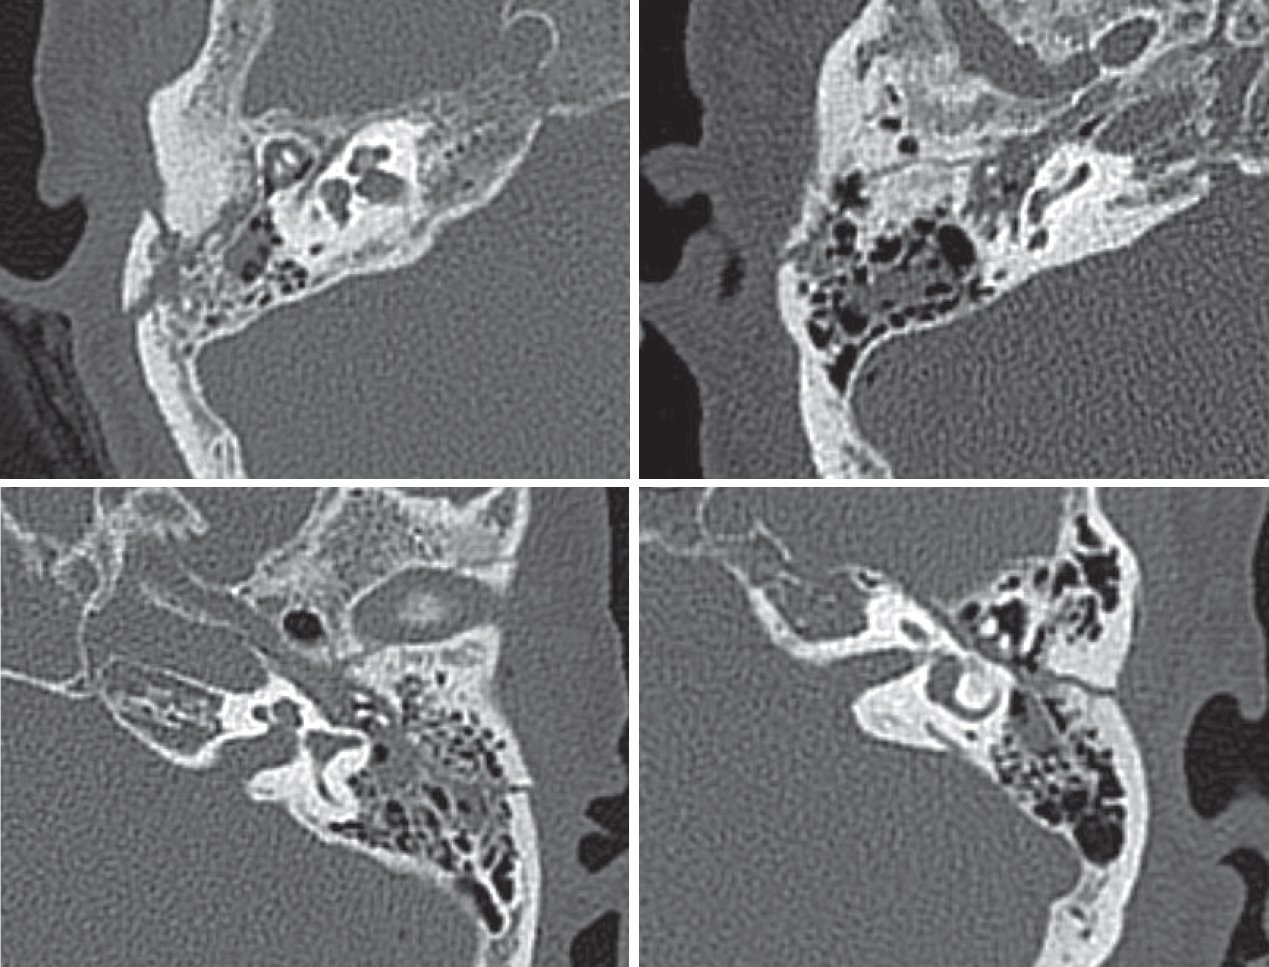

The presence of temporal bone fracture was confirmed by temporal bone CT (Fig. 1). Among the patients with temporal bone fracture, patients with otic capsule-disrupting fracture were excluded. Among the patients without temporal bone fracture, patients with factors that could induce BPPV such as head trauma were excluded. Patients with multiple canal involvement or canal conversion during CRPs were excluded. Clinical features of the patients and information about BPPV were collected from their medical records.